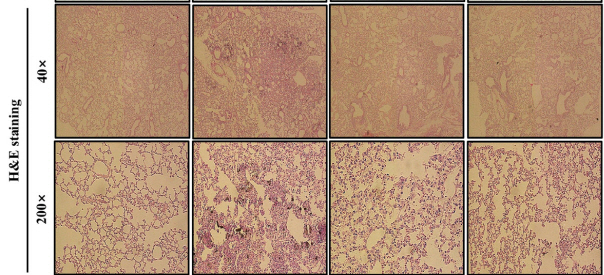

㈜에스앤디는 감태·감국 복합소재가 가진 가래·호흡곤란 완화 및 초미세먼지로 인한 염증지표 개선 효과를 과학적으로 입증했다.